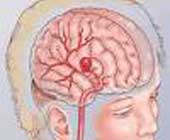

蛛网膜下腔出血 (英文:Subarachnoid hemorrhage, SAH), 病名,是指蛛网膜下腔中出血的现象。常见的病因是脑动脉畸形,动脉瘤,血液疾病等。

凡能引起脑出血的病因也能引起本病,但以颅内动脉瘤、动静脉畸形、高血压动脉硬化症、脑底异常血管网(moya-moya病)和血液病等为最常见。多在情绪激动或过度用力时发病。动脉瘤好发于脑底动脉环的大动脉分支处,以该环的前半部较多见。动静脉畸形多位于大脑半球大脑中动脉分布区。当血管破裂血流入脑蛛网膜下腔后,颅腔内容物增加,压力增高,并继发脑血管痉挛。后者系因出血后血凝块和围绕血管壁的纤维索之牵引(机械因素),血管壁平滑肌细胞间形成的神经肌肉接头产生广泛缺血性损害和水肿。另外大量积血或凝血块沉积于颅底,部分凝集的红细胞还可堵塞蛛网膜绒毛间的小沟,使脑脊液的回吸收被阻,因而可发生急性交通性脑积水,使颅内压急骤升高,进一步减少了脑血流量,加重了脑水肿,甚至导致脑疝形成。以上均可使患者病情稳定好转后,再次出现意识障碍或出现局限性神经症状。